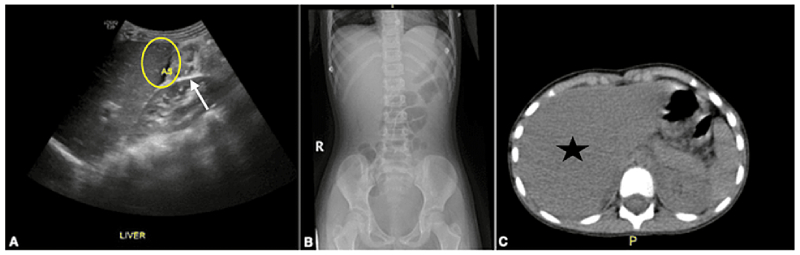

Bên cạnh đó nuôi cấy Salmonella dương tính từ máu hoặc phân là điều cần thiết để phân biệt viêm gan do nhiễm salmonella với các nguyên nhân khác gây viêm gan cấp tính. Siêu âm bụng, chụp cắt lớp vi tính (CT),… cũng có thể được chỉ định để kiểm tra tình trạng của gan.